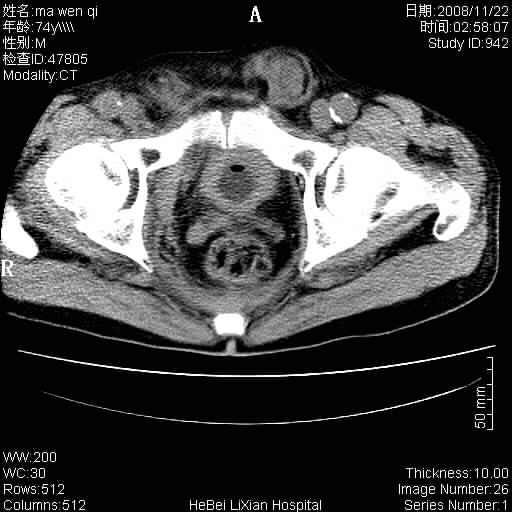

患者男 74岁.突然昏迷,休克6小时.血压70/30,头颅ct未见异常,既往体健.

补充病史,保留导尿10小时,尿袋内只有少许尿液,患者于住院后15小时后去世.

腹主动脉、双侧髂动脉夹层动脉瘤破裂出血进入腹腔。

考虑双侧髂a瘤,伴破裂出血

腹主动脉、双侧髂动脉夹层或动脉瘤破裂出血进入腹腔

1)考虑双侧髂动脉瘤并右侧动脉瘤破裂出血,右侧腹膜后及腹腔积血。2)双侧腹股沟疝。

支持(1)双侧髂动脉瘤并右侧动脉瘤破裂出血,右侧腹膜后及腹腔积血。(2)双侧腹股沟疝。

1)考虑,腹主动脉、双侧髂动脉夹层动脉瘤破裂伴右侧腹膜后及腹腔积血。2)双侧腹股沟疝。